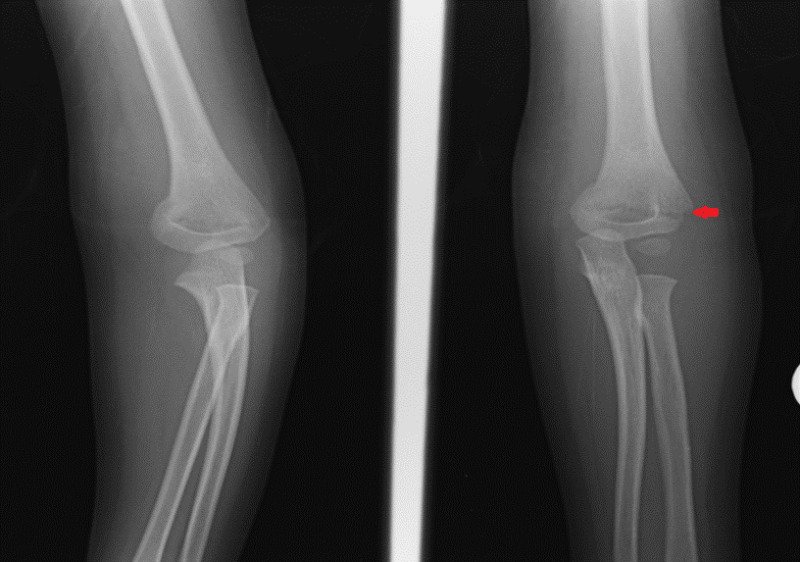

Radiological feature of Supracondylar fracture of humerus:

1) Obtain an AP and lateral view of the elbow.

2) A spectrum of abnormalities can be seen from mild cortical irregularity to complete displacement of the distal humeral fragment with loss of fracture continuity.

3) Often only a subtle fracture line will be seen.

4) Look for the presence of a posterior fat pad, prominent anterior fat pad or disruption of the anterior humeral line.